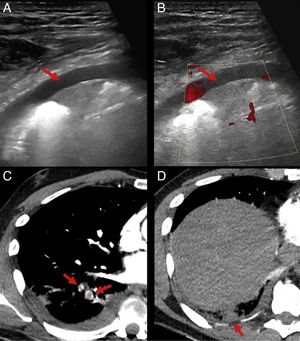

Hombre que consultó por tos, dolor pleurítico y fiebre (38,3°C). En la radiografía de tórax presentaba una consolidación en el lóbulo inferior derecho (LID) con borramiento de la silueta diafragmática. Con el diagnóstico de neumonía complicada se solicitó ecografía torácica, donde se observó una leve cantidad de derrame pleural y una consolidación subpleural de morfología triangular con base pleural (fig. 1A) sin presencia de señal doppler en su interior (fig. 1B), pudiendo corresponder a un infarto pulmonar. Se realizó angio-TAC torácico que confirmó la presencia de defectos de repleción en las arterias segmentaria posterobasal y laterobasal del LID (fig. 1C) con una opacidad subpleural y periférica en el segmento posterobasal del LID (fig. 1D), hipocaptante, correspondiente a un infarto pulmonar. El patrón ecográfico del TEP se ha descrito como presencia de «líneas A» con una sensibilidad del 81% y especificidad del 99% si se asocia a trombosis venosa profunda1. El infarto pulmonar puede identificarse como una lesión hipoecoica con forma de cuña y base pleural de bordes bien definidos2. En este caso la ecografía torácica en una sospecha inicial de neumonía complicada fue clave para llegar al diagnóstico correcto.